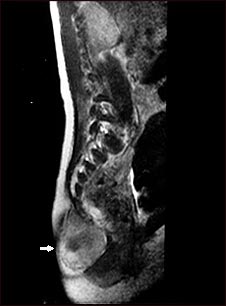

Teratoma - IRM

Esta IRM muestra un tumor (teratoma) en la base de la columna vertebral (se observa en el borde inferior izquierdo de la pantalla), situado en las áreas sacra y coxígea (área sacrocoxígea). Los teratomas se presentan al nacimiento y pueden contener pelo, dientes y otros tejidos.